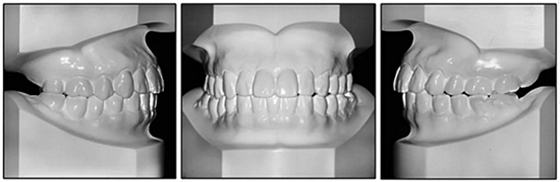

36歲;女性;尋求下頜左后方區(qū)域間隙管理的建議(圖1和圖2),通過(guò)治療獲得了良好的牙頜面效果(圖3和圖4)。她被診斷患有骨性I類和代償性牙性II類錯(cuò)合畸形,并且上頜左側(cè)尖牙缺失(圖1和2)。大約七年前,由于不可修復(fù)的齲齒,拔除了下頜左側(cè)第一和第二磨牙(圖5)。37相鄰的第三磨牙向近中移動(dòng)并傾斜入間隙,導(dǎo)致無(wú)牙頜間隙減小至約14 mm(圖2和圖5)。臨床和影像學(xué)評(píng)估顯示多發(fā)性齲損和在下頜右側(cè)567處有一不良的固定橋修復(fù)體(圖1和5)。此外,下頜左中切牙缺失,造成下頜中線向左側(cè)偏移約3 mm(圖1和圖2)?;颊咦栽V,她的右上第一前磨牙和左上尖牙在13歲時(shí)由其家庭牙醫(yī)拔除,因?yàn)樗鼈儽蛔枞筋a側(cè)萌出(圖1)。上頜第二磨牙缺失(未知病因),并且相鄰的第三磨牙已經(jīng)轉(zhuǎn)移到第二磨牙間隙中。如補(bǔ)充材料所示,美國(guó)正畸學(xué)差異指數(shù)DI是28分。種植體部位(下頜左側(cè)和右側(cè)第一磨牙)由于復(fù)雜性得到額外4分(補(bǔ)充材料)。

圖1. 治療前面部和口內(nèi)照片